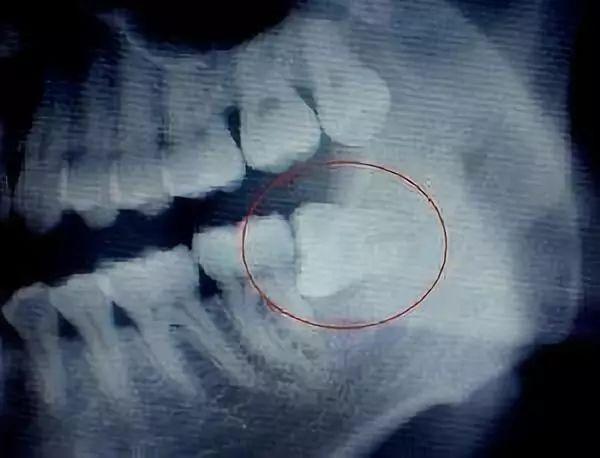

一些長(zhǎng)得比較“正”智齒,它的拔除過(guò)程相對(duì)比較輕松,且操作比較簡(jiǎn)單,耗材也較少,所以收費(fèi)也就不會(huì)太高。但有一些智齒,它是傾斜長(zhǎng)的,或者是水平長(zhǎng)的,或者是埋在骨頭里的,甚至壓著神經(jīng)管的,這時(shí)候就需要將軟組織切開(kāi),做周圍骨頭的去除;也有一些,為了盡量少去骨,而進(jìn)行微創(chuàng)手術(shù)拔除的,需要把智齒切割成一小塊一小塊,然后逐塊取出,這種智齒拔除手術(shù)的難度和對(duì)醫(yī)生的操作要求都相對(duì)較高,因此價(jià)格也會(huì)相應(yīng)地提升。綜上所述,拔除一顆智齒需要花多少錢(qián),還需要根據(jù)這顆智齒拔除的難易程度以及患者口腔的具體情況而定。一般情況下,拔除一顆智齒的價(jià)格介乎于幾百元到幾千元之間

一顆橫生的智齒,鉗子是搞不出來(lái)的。醫(yī)生可以拿出鍾鑿把它劈開(kāi)搞出來(lái),也可以拿出渦輪機(jī)把它磨開(kāi)搞出來(lái),對(duì)患者帶去的影響是一樣的嗎?前者會(huì)造成患者心理恐慌,加重關(guān)節(jié)負(fù)荷,后者會(huì)帶來(lái)更高的術(shù)后感染、局部反應(yīng)風(fēng)險(xiǎn),能輕易地判斷說(shuō)哪個(gè)方法更先進(jìn)嗎?只有適合的,沒(méi)有好的,這個(gè)背后體現(xiàn)的是醫(yī)生的經(jīng)驗(yàn)和人文關(guān)懷。